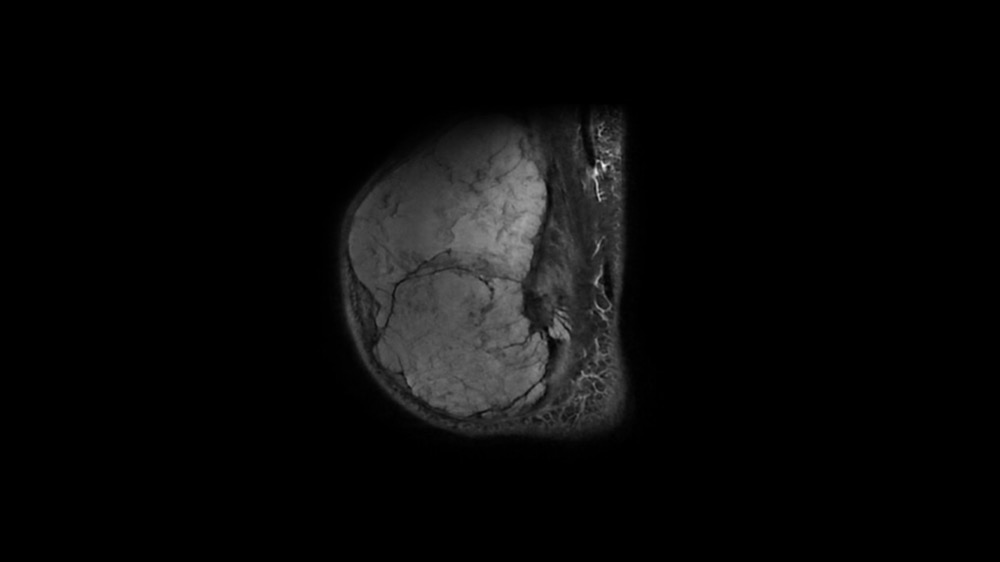

Bone Club

Bernard Hollier 18/05/2022